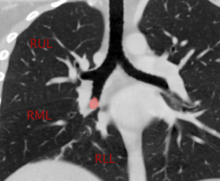

A dedicated chest computed tomography (CT) was obtained, clearly visualizing the lesion within the bronchus intermedius, with what appeared to be adequate margins to facilitate a stapling device. However, at the time of bronchoscopy, the lobulated endobronchial mass was located about 1 cm from the takeoff of the right upper lobe bronchus and was obstructing approximately 90% of the bronchial lumen. Bronchial washings and brushings were taken, and pathology was consistent with a well-differentiated neuroendocrine tumor, also called a typical carcinoid tumor, with Ki-67 <3%. A DOTA-TATE positron emission tomography/CT showed an isolated lesion in the right lung with an standardized update value max of 38. There was no locoregional adenopathy or evidence of distant disease.